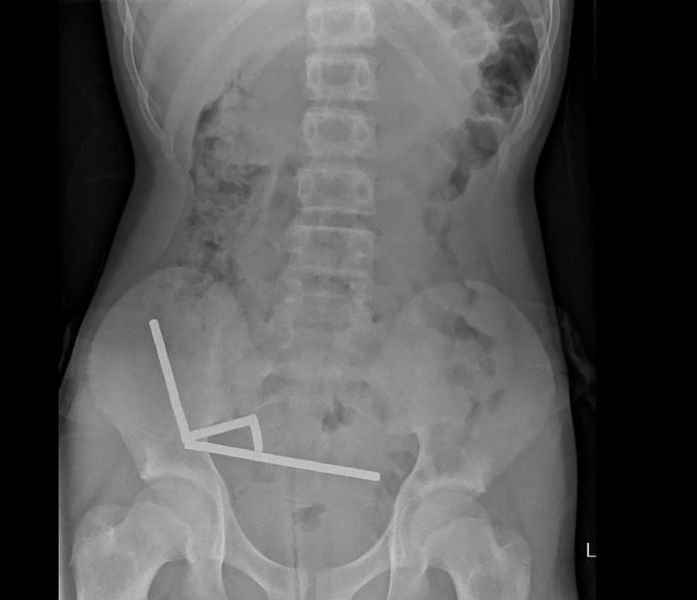

I-X-ray itshengise ukuthi omazibuthe babehlangene ndawonye belandelana ngolayini abane abaqondile ngaphakathi emathunjini ale ngane.

“Labo mazibuthe babukeka engathi basezingxenyeni ezihlukene zamathumbu asenamathelene ngenxa yamandla kamazibuthe,” basho njalo.

Odokotela bathi incindezi yomazibuthe ibangele i-necrosis okungukufa kwezicubu – ezindaweni ezine zamathumbu amancane omfana kanye ne-caecum, okuyingxenye yamathumbu amakhulu.